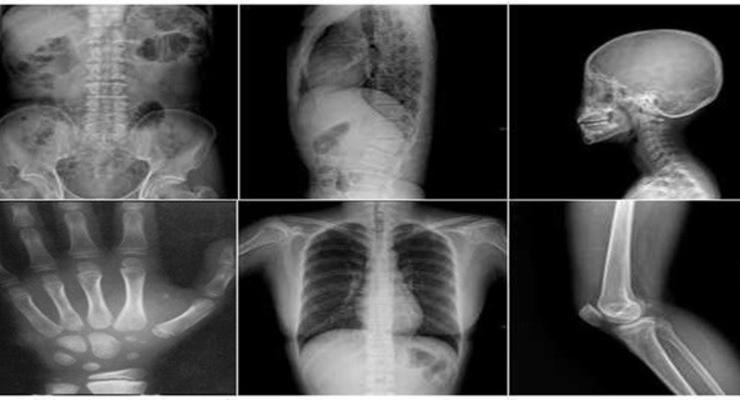

Sigara içenlerde kırıklar kolay iyileşmez!

Kırıkların iyileşme süreci, yaşa, kırığın durumuna göre değişiklik gösteriyor. Son yapılan araştırmalar bu nedenlerin arasına bir yenisini daha ekledi. Sigara içen insanlarda kırıkların geç iyileştiğini ifade eden Türkiye Hastanesi Ortopedi ve Travmatoloji doktorlarından Prof. Dr. İrfan Öztürk, “Sigara kırık iyileşmesini önlüyor. Sigara, mikro damarlanma sistemini ve kemik yapan hücreleri bozduğu için kırık uçlarında beslenme bozukluğuna ve bu nedenle kaynamamaya sebep oluyor” dedi.

Sigaranın kırık uçlarında beslenme bozukluğuna neden olduğu ifade eden Prof. Dr. İrfan Öztürk, bu durumun kaynamayı engellediği için cerrahların bu ameliyatlardan kaçındığını ifade etti. Prof. Dr. Öztürk, “Sigara kullanan hastalarda kaynama gecikmesi veya kaynamama süreci olabileceği için bazı cerrahlar bu hastaları ameliyat etmekten kaçınmaktadırlar. En basit kırıktan komplike kırıklara kadar kırık iyileşmesi çok önem arz etmektedir. Kırık kaynamasını etkileyen hastaya ve hekime bağlı birçok faktör bulunmaktadır. Hekimin görevi, hastaya bağlı faktörleri önceden tespit edip gerekli önlemleri almak, riskleri hasta ile paylaşırken kendi bilgi ve becerisini hastaya en efektif şekilde sunmak olmalıdır” diye konuştu.

KIRIK KEMİK NASIL İYİLEŞİR?

Basit bir kırığın ortalama 3 haftada iyileşebileceğini belirten Öztürk, “Uyluk ve kaval kemiği kırıklarının iyileşmesi ise 2 ila 4 ay arasında değişiyor. Kemik dokusunun destek, koruma, hareket, yağ ve kalsiyum depolama, kan hücresi oluşturma ve boy uzamasına etkisi gibi önemli görevleri vardır. Oluşan kırıklar sonucunda bu görevlerde aksama meydana gelebilir. Meydana gelen bir kırık, “Kallus” adı verilen yeni kemik dokusunun oluşması ile iyileşir. Ancak bazı durumlarda yeterli kallus dokusunun oluşmaması neticesinde kırıkta kaynama süresi uzayabilir veya kırığın hiç kaynamama durumu ile karşılaşılabilir.

Bununla beraber kırık iyileşmesinde kemiğin yumuşak doku tutunumlarının zarar görmesi, kırık tedavisi stabilitesinin yetersizliği, bazı anatomik bölgeler, kırığa sebep olan enerji gücünün yüksekliği kemik kaybı oluşma miktarı gibi mekanik nedenler ve ileri hasta yaşı, hastalıklara bağlı düşkünlük, beslenme bozukluğu, hormon dengesizliği, sinir fonksiyonlarının azalması, kan dolaşımının azalması, sigara kullanımı, enfeksiyon varlığı, kırıkta kemik kaybı olması gibi biyolojik neden etkili olmaktadır” ifadelerini kullandı.

Yaşlı insanlarda hormonların, adale tonusunun ve damarlanmanın azalması nedeniyle kırık iyileşmesinin zor olduğunu söyleyen Öztürk, “Diyabet, cushing, hipotiroid, periferik vaskülopatiler gibi hastalıklar ile radyoterapi ve kemoterapi uygulamaları da kırık iyileşmesinin sürecine zarar verir” dedi.